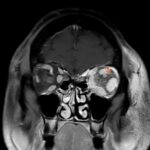

Orbital compartment syndrome (OCS) is an ophthalmologic emergency due to an acute rise in intra-orbital pressure and can result in permanent vision loss, oftentimes requiring emergent surgical decompression. Orbital compartment syndrome most commonly occurs due to recent trauma and is often easily diagnosed by history and physical exam. However, there are other causes of OCS where a more subacute/chronic rise in pressure can lead to an atypical presentation. This is a case report of a 48-year-old male who presented with left eye pain and swelling for the past 6 months. The patient had seen two ophthalmologists prior to his emergency department (ED) presentation who had prescribed him an antibiotic ointment, oral steroids, and steroid eye drops. The physical exam in the ED was concerning for increased intra-ocular pressure (IOP) and decreased vision. Ophthalmology was consulted and requested magnetic resonance angiography (MRA) to assess a vascular etiology given tortuous retinal vasculature. Emergent surgical decompression was deferred due to chronicity of symptoms, and patient was started on dorzolamide/timolol and brimonidine eye drops as well as intravenous (IV) acetazolamide with subsequent improvement in IOP. Imaging revealed a left carotid-cavernous sinus fistula (CCF), and the patient was admitted to neurosurgery. Patient successfully had an embolization with subsequent normalization of IOP and improvement of symptoms. This case is a good example of how non-traumatic causes of OCS can lead to misdiagnosis and how surgical decompression could potentially be deferred in subacute OCS.